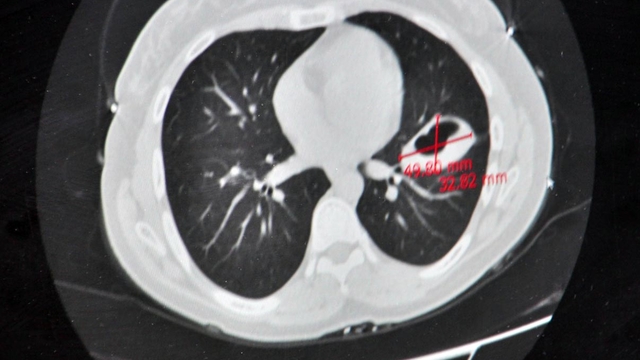

Hastalığın başlarda kistin küçük olduğu dönemlerde uzun yıllar boyunca belirtisiz seyredebileceğini söyleyen Perincek, “Fakat kist büyüdükçe, bulunduğu bölgeye ve oluşturduğu basıya göre belirtiler ortaya çıkar. Kistler en sık karaciğer ve akciğerlerde görülürler. Nadiren dalak, karın zarı (periton), böbrek, kemik, göz yuvası, beyin, kalp ve yumurtalıklara da yerleşebilir. Karaciğer yerleşiminde karnın sağ üst kısmında ağrı, bulantı, kusma ve bazen kaşıntı, sarılık gibi belirti görülür. Akciğer tutulumunda solunum sıkıntısı, öksürük, ağızdan kan gelmesi ve göğüs ağrısı olabilir. Diğer organ ve sistem tutulumlarında da bu bölgelere ait tablolar ortaya çıkar. Örneğin kafa içi tutulumlarda; baş ağrısı, kusma, şuur kayıpları görülebilir. Kalp tutulumunda kalp ritim bozuklukları, enfarktüs bulguları, hatta kalp duvarında yırtılma olabilir. Kemik tutulumlarında kırıklar olabilir. Kist patladığında alerjik reaksiyonlar ortaya çıkabilir” diye konuştu.